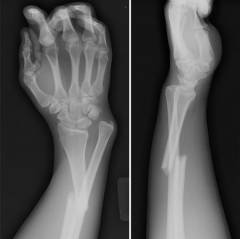

Перелом лучевой кости определяется клиническим обследованием и рентгенографией, которые дают полную информацию для подтверждения диагноза и контроля лечения.

Рентгенографические методы обследования

Рентгеновские лучи — это ионизирующее электромагнитное излучение, проникающее через мягкие ткани и поглощаемое плотными структурами. При рентгенографии конечности можно увидеть контуры костей и выявить затемнения, указывающие на патологии или изменения.

- Простая радиография или радиоскопия. Простая радиография включает кратковременное просвечивание конечности рентгеновскими лучами с получением изображения на пленке. Радиоскопия отображает изображение в реальном времени на экране. В травматологии чаще используется простая радиография в двух проекциях — переднезадней и боковой, что позволяет детально рассмотреть область и снизить количество ошибок.

Радиологические методы обследования выявляют признаки перелома лучевой кости:

- дефект с пониженной интенсивностью рентгеновской тени (трещина);

- косая, поперечная, винтообразная или продольная линия перелома;

- множественные изолированные затемнения в области кости (оскольчатый перелом);

- изменение оси кости в месте перелома;

- отечность окружающих тканей;

- смещение суставных поверхностей;

- вывих локтевой кости.